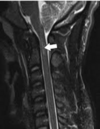

Qual a indicação de solicitação de RNM no caso de TRM ?

avaliação de déficit neurológico não explicado, avaliação de hematoma e edema e suspeita de lesão ligamentar.